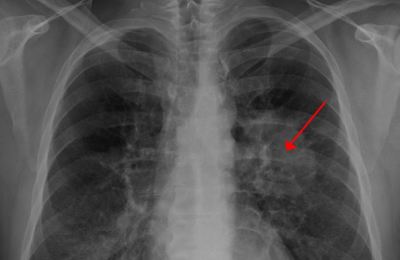

폐렴 증상 폐렴 증상

폐렴 증상 3. 호흡 곤란 및 숨 가쁨

폐에 염증이 생기면 산소 교환이 어려워져

숨이 차고 가슴이 조이는 느낌,

또는 평소보다 가쁜 숨, 짧은 호흡이 나타날 수 있어요.